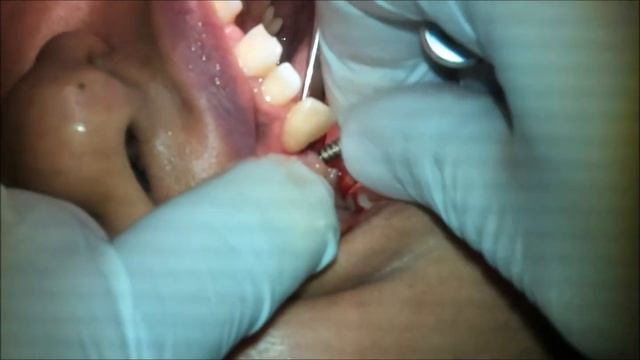

Dr. Aghyad : Closed sinus lift & dental implant placement смотреть онлайн

07:08

Dr. Aghyad : Closed sinus lift & dental implant placement

Hydraulic sinus lift technique using DASK Dentium sinus kit смотреть онлайн

05:15

Hydraulic sinus lift technique using DASK Dentium sinus kit

Dental Implant Using Ridge Expansion and Crestal Sinus Lifting смотреть онлайн

07:52

Dental Implant Using Ridge Expansion and Crestal Sinus Lifting